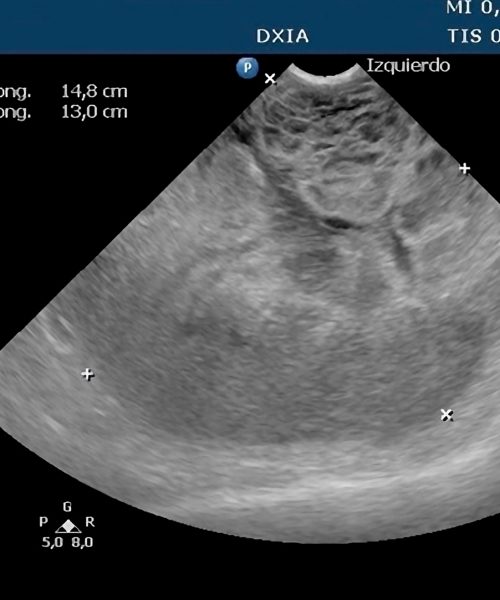

Ofrezco especialización en ecografía veterinaria y una colaboración integral basada en vuestro historial clínico.

Valido la precisión diagnóstica comparando las imágenes ecográficas con los hallazgos quirúrgicos reales.

Garantizo transparencia y confianza exhibiendo en este apartado casos reales con su correlación intraoperatoria documentada.